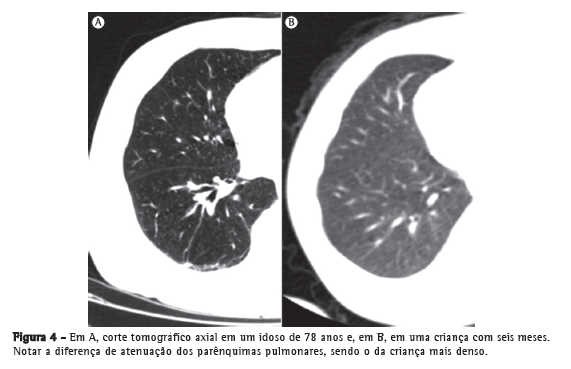

Turner et al.(34) relataram que, em indivíduos com idades entre 20 e 60 anos, a relação do peso do pulmão com o peso corporal não diminui com o envelhecimento, o que sugere ou pouca/nenhuma destruição do pulmão ou a substituição de tecidos.(34,36,37) Durante o curso do envelhecimento, os ductos alveolares aumentam seu diâmetro, e os alvéolos tornam-se mais largos e rasos. Após a quarta década de vida, uma parte das fibras elásticas dos bronquíolos respiratórios e alvéolos degenera, o que diminui sua complacência.(38) Tais mudanças são mais marcantes ao redor dos ductos alveolares. Consequentemente, ocorre a dilatação desses ductos, seguida pelo alargamento dos espaços aéreos.(32) Esse alargamento é notavelmente homogêneo, ao contrário da distribuição irregular de alargamento do espaço aéreo no enfisema (Figuras 3 e 4).

Estudos morfométricos têm mostrado um aumento progressivo da distância média entre as paredes dos espaços aéreos e uma diminuição da superfície das paredes do espaço aéreo, por unidade de volume pulmonar.(34,39,40) Essas alterações têm início na terceira década de vida e progridem de forma linear e contínua, resultando em uma diminuição da superfície das paredes do espaço aéreo de 25-30% em nonagenários.(39,40) Embora essas mudanças sejam histologicamente diferentes daquelas do enfisema pulmonar, no qual há a destruição das paredes alveolares, elas resultam em mudanças semelhantes na complacência pulmonar. Da mesma forma que o enfisema pulmonar, essas alterações ocasionam uma redução dos tecidos de suporte em torno das vias aéreas, onde há uma tendência ao colapso das pequenas vias aéreas (< 2 mm) e consequente alteração no fluxo aéreo. Tal fenômeno de alterações morfoestruturais no parênquima pulmonar associado ao envelhecimento tem sido denominado na literatura como "enfisema senil" (Figura 3).(38)

No estudo por TC do parênquima pulmonar, identificam-se alguns achados radiológicos muito comuns em idosos, e especula-se que eles tenham relação com as alterações do colágeno. Esses achados são atelectasias laminares, na maioria das vezes posteriores e basais, localizadas em áreas pendentes dos pulmões (Figura 5); espessamentos lineares subpleurais (Figura 6); áreas de aprisionamento aéreo (Figura 7); espessamento e ectasia brônquica (Figura 8); e cistos pulmonares.(41,50-53)